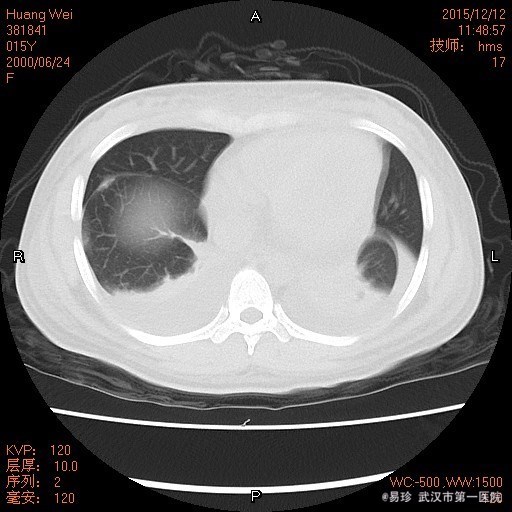

查体:T:38.5℃ P:102次/分 R:29次/分 BP:156/96mmHg 鼻部皮肤见散在淡红色皮疹,双小腿皮肤见色素沉着,未见皮疹、瘀斑。右颌下扪及一黄豆大小淋巴结,活动可,无压痛,质中,余浅表淋巴结未触及肿大。脸部淡红色碟形红斑,心肺听诊未闻及异常,腹软,无压痛及反跳痛,双下肢无浮肿。 辅查: 1.HGB85g/L、尿蛋白2+、尿潜血3+,血白蛋白22.9g/L、补体C3 0.09g/L、补体C4 0.02g/L,血肌酐151umol/l,Coombs试验阳性,ANA滴度1:3200,dsDNA阳性” 2.骨髓涂片提示:骨髓增生活跃,粒、红系比例正常,铁染色示缺铁,建议做铁蛋白检查。 3.胸片提示双下肺炎症。

诊断:1、I型呼吸衰竭;2、急性左心衰;3、咯血查因:狼疮性肺炎可能;4、肺部感染;5、系统性红斑狼疮,狼疮性肾炎,急性肾损伤,狼疮血液系统损害,狼疮心脏损害 左房左室增大 二尖瓣关闭不全(轻度) 三尖瓣关闭不全(轻度)心包积液 心功能Ⅲ级 治疗:入院后予以甲强龙、丙球抑制免疫反应,持续血透、抗感染、降压、面罩吸氧等治疗。但患者仍出现进行性血压升高、呼吸循环功能衰竭。后家属强烈要求出院并回当地治疗。